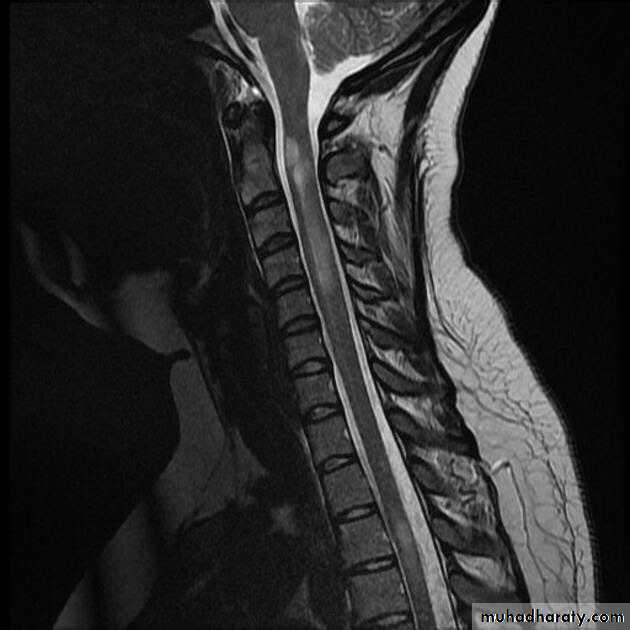

myelitis can be severe and transverse (rare in MS) and is typically longitudinally extensive, involving three or more contiguous vertebral segments

A T2-weighted MRI image of her spinal cord shows a lesion extending from T1 to T5 and affecting the central cord. The lesion shows patchy enhancement with gadolinium.

Neuroimaging characteristics are critical for diagnosis. Identification of an intramedullary cord lesion, especially postgadolinium enhancement, is very helpful in a diagnosis of myelitis

1. MRI of spinal cord with and without contrast (exclude compressive causes).